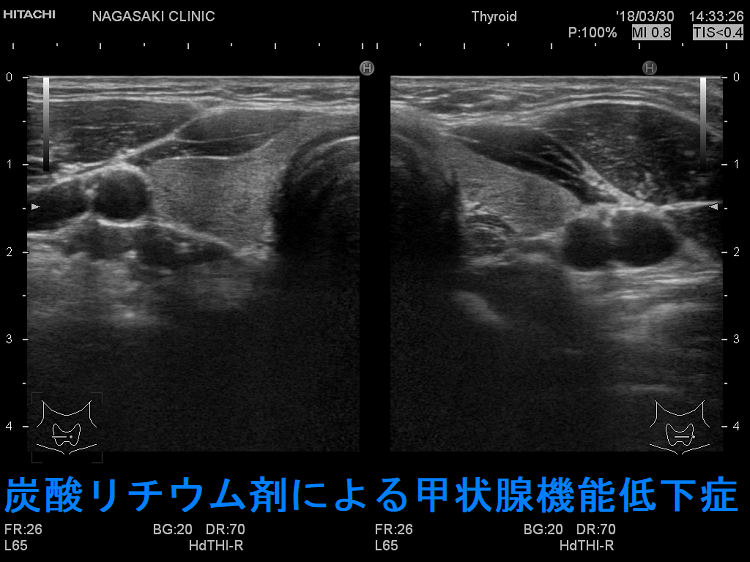

薬剤性甲状腺異常[GnRH,エストロゲン誘導体(SERM),黄体ホルモン剤][破壊性甲状腺炎(薬剤性無痛性甲状腺炎) 橋本病 長崎甲状腺クリニック 大阪]

- 炭酸リチウム(商品名リーマス)と甲状腺